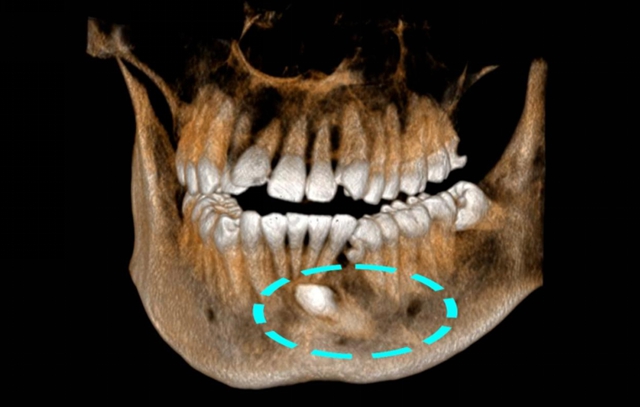

但23岁的小陈到西南医科大学附属中医医院口腔诊疗中心就诊时,却让彭培钊医生捏了一把汗——他的一颗尖牙竟“迷路”钻进了下颌骨深处,紧贴着前牙牙根,周围还缠绕着少见的粗大血管,堪称一颗潜伏的“口腔地雷”。

彭培钊发现小陈左侧下颌尖牙是颗早该脱落的乳牙,正常应该长出来的恒牙尖牙反而“躲”在了下颌骨里,牙冠直对着下前牙的牙根,只有毫厘之差。

更棘手的是,这颗埋伏牙周围还绕着一支很少见的直径0.9mm血管,比常见的颌骨内血管粗不少。

通过数字化三维重建技术,精准定位埋伏牙与神经血管的位置关系。